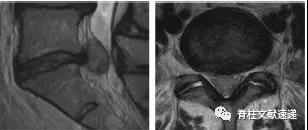

图注:钙化椎间盘及骨赘导致脊液漏

图注:一位47岁女性因钙化椎间盘后方骨赘导致硬脑膜撕裂、脑脊液漏和颅内压过低。